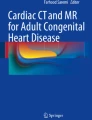

All three valves are a porcine pericardial tissue valve mounted on a self-expanding nitinol frame and have proximal and distal flares that anchor the valve in the right ventricular outflow tract. The Venus P-valve is one of the leading valves, which has an asymmetrical covering design, in which the pulmonary artery end flare is not covered, permitting unobstructed flow into the branch pulmonary arteries. Currently, the Venus P-valve is available in diameters from 16 to 36 mm with 2-mm increments, with each diameter available in 20-, 25-, 30- and 35-mm straight section lengths (Fig. 1). The valve can be implanted in the RVOTs, whose narrowest diameter is up to 33–34 mm, for which a 36-mm-diameter valve can be implanted, which is the largest diameter valve currently available [53, 54••].

Deployment of the flared Venus P-valve. a Angiogram in the main pulmonary artery showing severe pulmonary regurgitation. b Positioning of the distal carrot of the Venus P-valve in the left pulmonary artery (LPA) using fusion imaging. c The deployment starting position in the proximal LPA. d, e After exposing the distal flare, the system is pulled free from the LPA origin before gradually deploying the rest of the valve frame. f Final angiogram after Venus P-valve implantation showing no pulmonary regurgitation